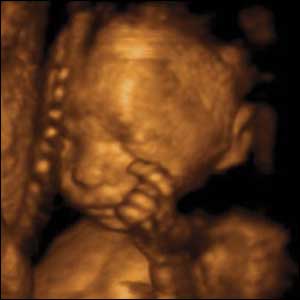

An abortionist describes how hard it is to remove the baby’s skull when doing an abortion.

“When one does a D&E, technically one of the challenges is to remove the fetal skull, partly because it is relatively large, partly because it is relatively calcified, and it is difficult to grasp on occasion.”

Testimony of abortionist Dr Timothy Johnson, National Abortion Federation, et. al. v. Ashcroft, U.S. District Court, Southern District of New York, March 31, 2004.

In a second trimester D & E procedure, the baby is decapitated and dismembered. Generally, the head (with the skull) is the last to be removed. Read a doctor’s description of the D & E procedure here.